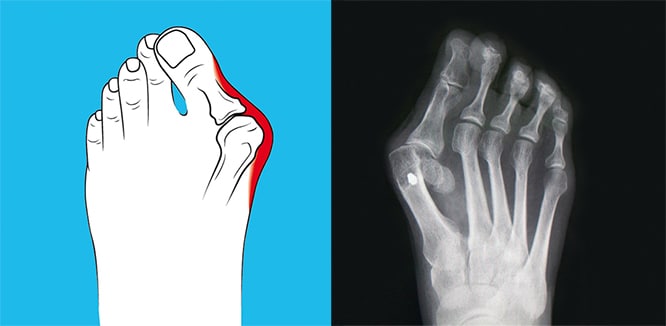

Halluks valgus neden olur. Halluks valgus ayak başparmağının diğer parmaklara doğru eğilmesi ve başparmağın altındaki tarak kemiğinin de ters yönde çıkıntı yapması ile kendini göstermektedir. Nasıl bir cerrahi yöntem uygulanacağı halluks valgus un derecesine göre belirlenir. Halluks valgus neden olur. Halluks valgusun gelişiminde rol oynayan birçok neden olabilir.

Hallux valgus tek bir deformite tipi veya tek bir hastalık olmadığından her halluks valgus a da aynı ameliyat yapılamaz. Görüntü olarak kişiyi rahatsız eden bu sorun ağrıya da neden olduğu için kişinin hayat kalitesini de oldukça düşürür. Başparmak çıkıntısı belirtileri ve tedavisi hallux valgus hv deformitesi ilk olarak 1871 de carl huster tarafından tanımlanmış ve birinci ayak parmağı yavaş yavaş içe doğru dönerken tarak kemiği dışa doğru döner ve normalde hiç görülmemesi gereken çıkıntı direkt görülür hale gelir. Halluks valgus ayak başparmağının dışa doğru dönerek ikinci parmağa doğru yakınlaşmasıyla karakterize bir şekil bozukluğudur başparmağın üstü ikinci parmağa doğru yaklaşırken dış tarafında da bir şişlik meydana gelir.